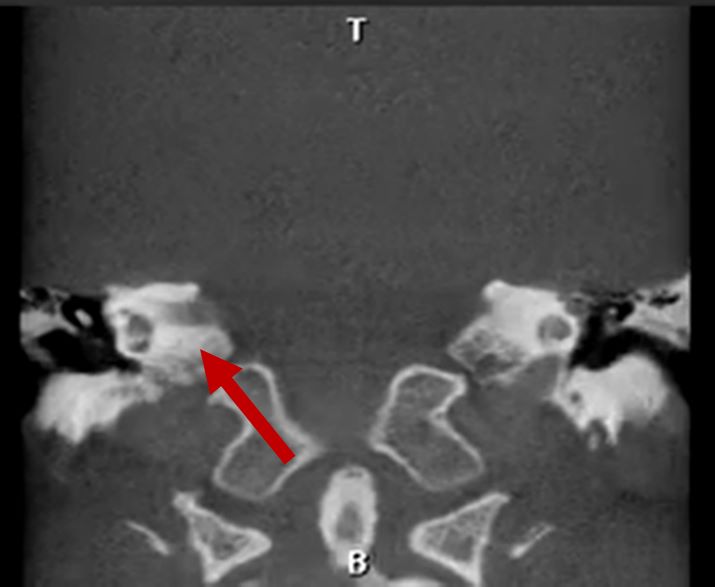

Middle ear deformities

2D CT scan showing deformed middle ear structure

Radiographical features source 8